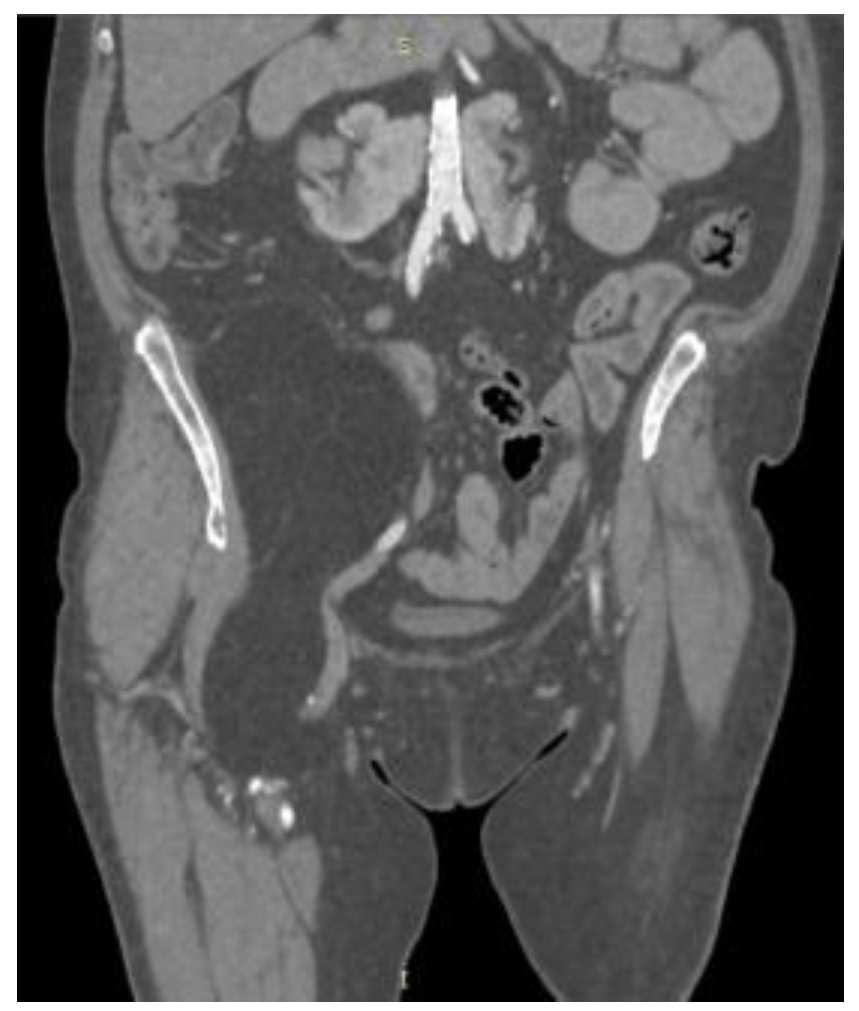

2. Case Presentation